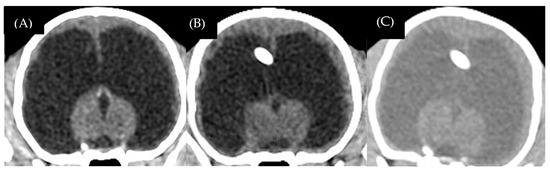

| 1 | Crossbreed | male | 2 | 2.4 | 3 | Mesencephalic aqueduct stenosis | 2.94 | 142.10 | 60 | 57.77 | Bilateral subdural hematoma and empyema |

| 2 | American Pitbull | male | 4 | 13.7 | 8 | Obstruction of interventricular foramen | 2.57 | 205.40 | 98.60 | 51.99 | Bilateral subdural hematoma and empyema |

| 3 | American Bully | male | 6 | 9.7 | 4 | Mesencephalic aqueduct stenosis | 3.68 | 139 | 7.57 | 94.55 | Bilateral subdural hematoma and empyema |

| 4 | Jack Russel Terrier | male | 6 | 1.6 | 12 | Mesencephalic aqueduct stenosis | 2.20 | 132 | 57.70 | 56.28 | Bilateral subdural hematoma |

| 5 | Chihuahua | female | 12 | 2.7 | 24 | Mesencephalic aqueduct stenosis with arachnoid cyst | 2.21 | 52.20 | 46.10 | 11.68 | Not detectable |

| 6 | Chihuahua | male | 5 | 1.4 | 6 | Obstruction of the lateral apertures with encephalitis | 8.80 | 49.70 | 45.30 | 8.85 | No detectable |

| 7 | Chihuahua | female | 48 | 2.5 | 48 | Obstruction of the lateral apertures with meningoencephalitis of unknown origin | 5.88 | 16.40 | 13.40 | 18.29 | No detectable |

| 8 | Chihuahua | male | 10 | 3.7 | 32 | Post-traumatic | 7.35 | 11 | - | - | - |